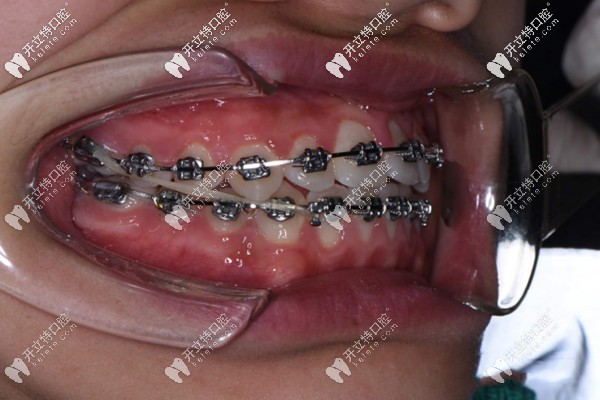

簡單看一下使用全同步帶狀牙套矯正的案例

牙齒問題:地包天影響美觀,安氏三類錯領(lǐng),骨性三類。

矯正過程:使用全同步帶狀弓矯治器,歷時一年左右。

使用全同步帶狀牙套矯正的案例